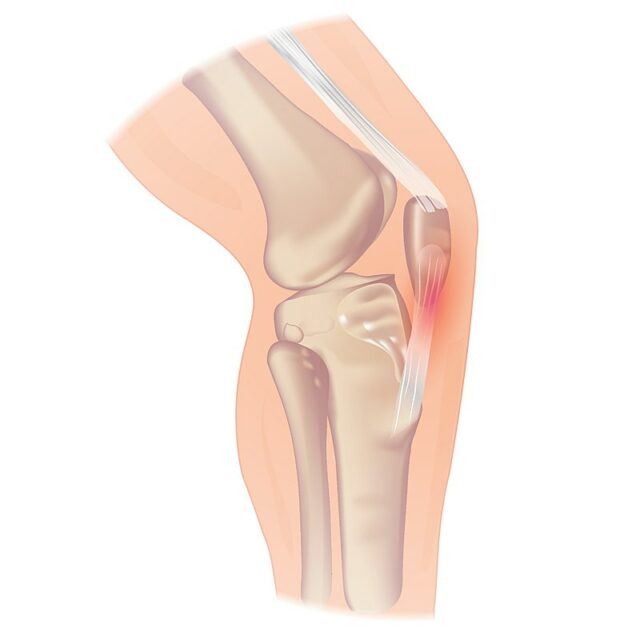

Die Patellarsehnentinopathie kann am unteren Pol der Kniescheibe auftreten, aber auch am Sehnenansatz an der Tuberositas tibiae, was seltener ist. Wenn ein Patient über Schmerzen an der Basis der Kniescheibe klagt, besteht der Verdacht auf eine Quadrizeps-Tendinopathie.

Eine Fettpolsterreizung äußert sich in der Regel durch diffuse Schmerzen und wird in der Regel durch eine Überstreckung des Knies verschlimmert. Bei jungen Sportlern zu Beginn der Pubertät müssen Sie die Pathologien der Wachstumsfugen im Hinterkopf behalten: Die häufigste ist die Osgood-Schlatter-Krankheit, eine Überlastungsverletzung, die durch eine Verknöcherung des Knochens entlang der Wachstumsplatte am Tuberculum tibiale gekennzeichnet ist. In der schwersten Version kann Osgood Schlatter zu einer nicht verschmolzenen Tuberositas tibiae Wachstumsplatte führen. Sinding Larsen Johannson ist das Äquivalent zu Osgood Schlatter, nur dass jetzt die Spitze der Kniescheibe betroffen ist.